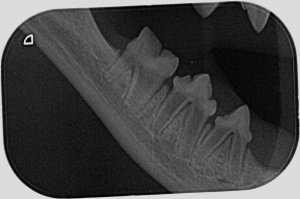

Ich hab zwar hier schon einige röntgenzahnbilder gesehen wo von Knochenabbau die rede war, deswegen hatte ich die Stellen markiert wo es (für mich ) auch so aussah, aber wahrscheinlich ist das in Ordnung so. Ich hoffe ja dass sich dazu noch jemand meldet und mir grünes Licht gibt.